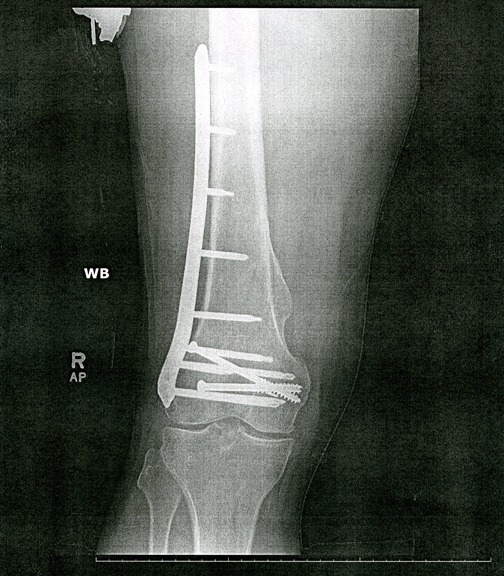

To the left is an x-ray of my leg as it has been since January, 2002.  The bracket depicted above was attached to my right femur with numerous screws to stabilize it during the original recovery period.  To the right is an x-ray of my leg today (literally, it was taken today, September 2, 2014).  The one remaining screw was so deeply embedded that my surgeon couldn't remove it.  He said that should knee replacement surgery become necessary, that's when it will go.  In the meantime it's an interesting if inaccessible souvenir.